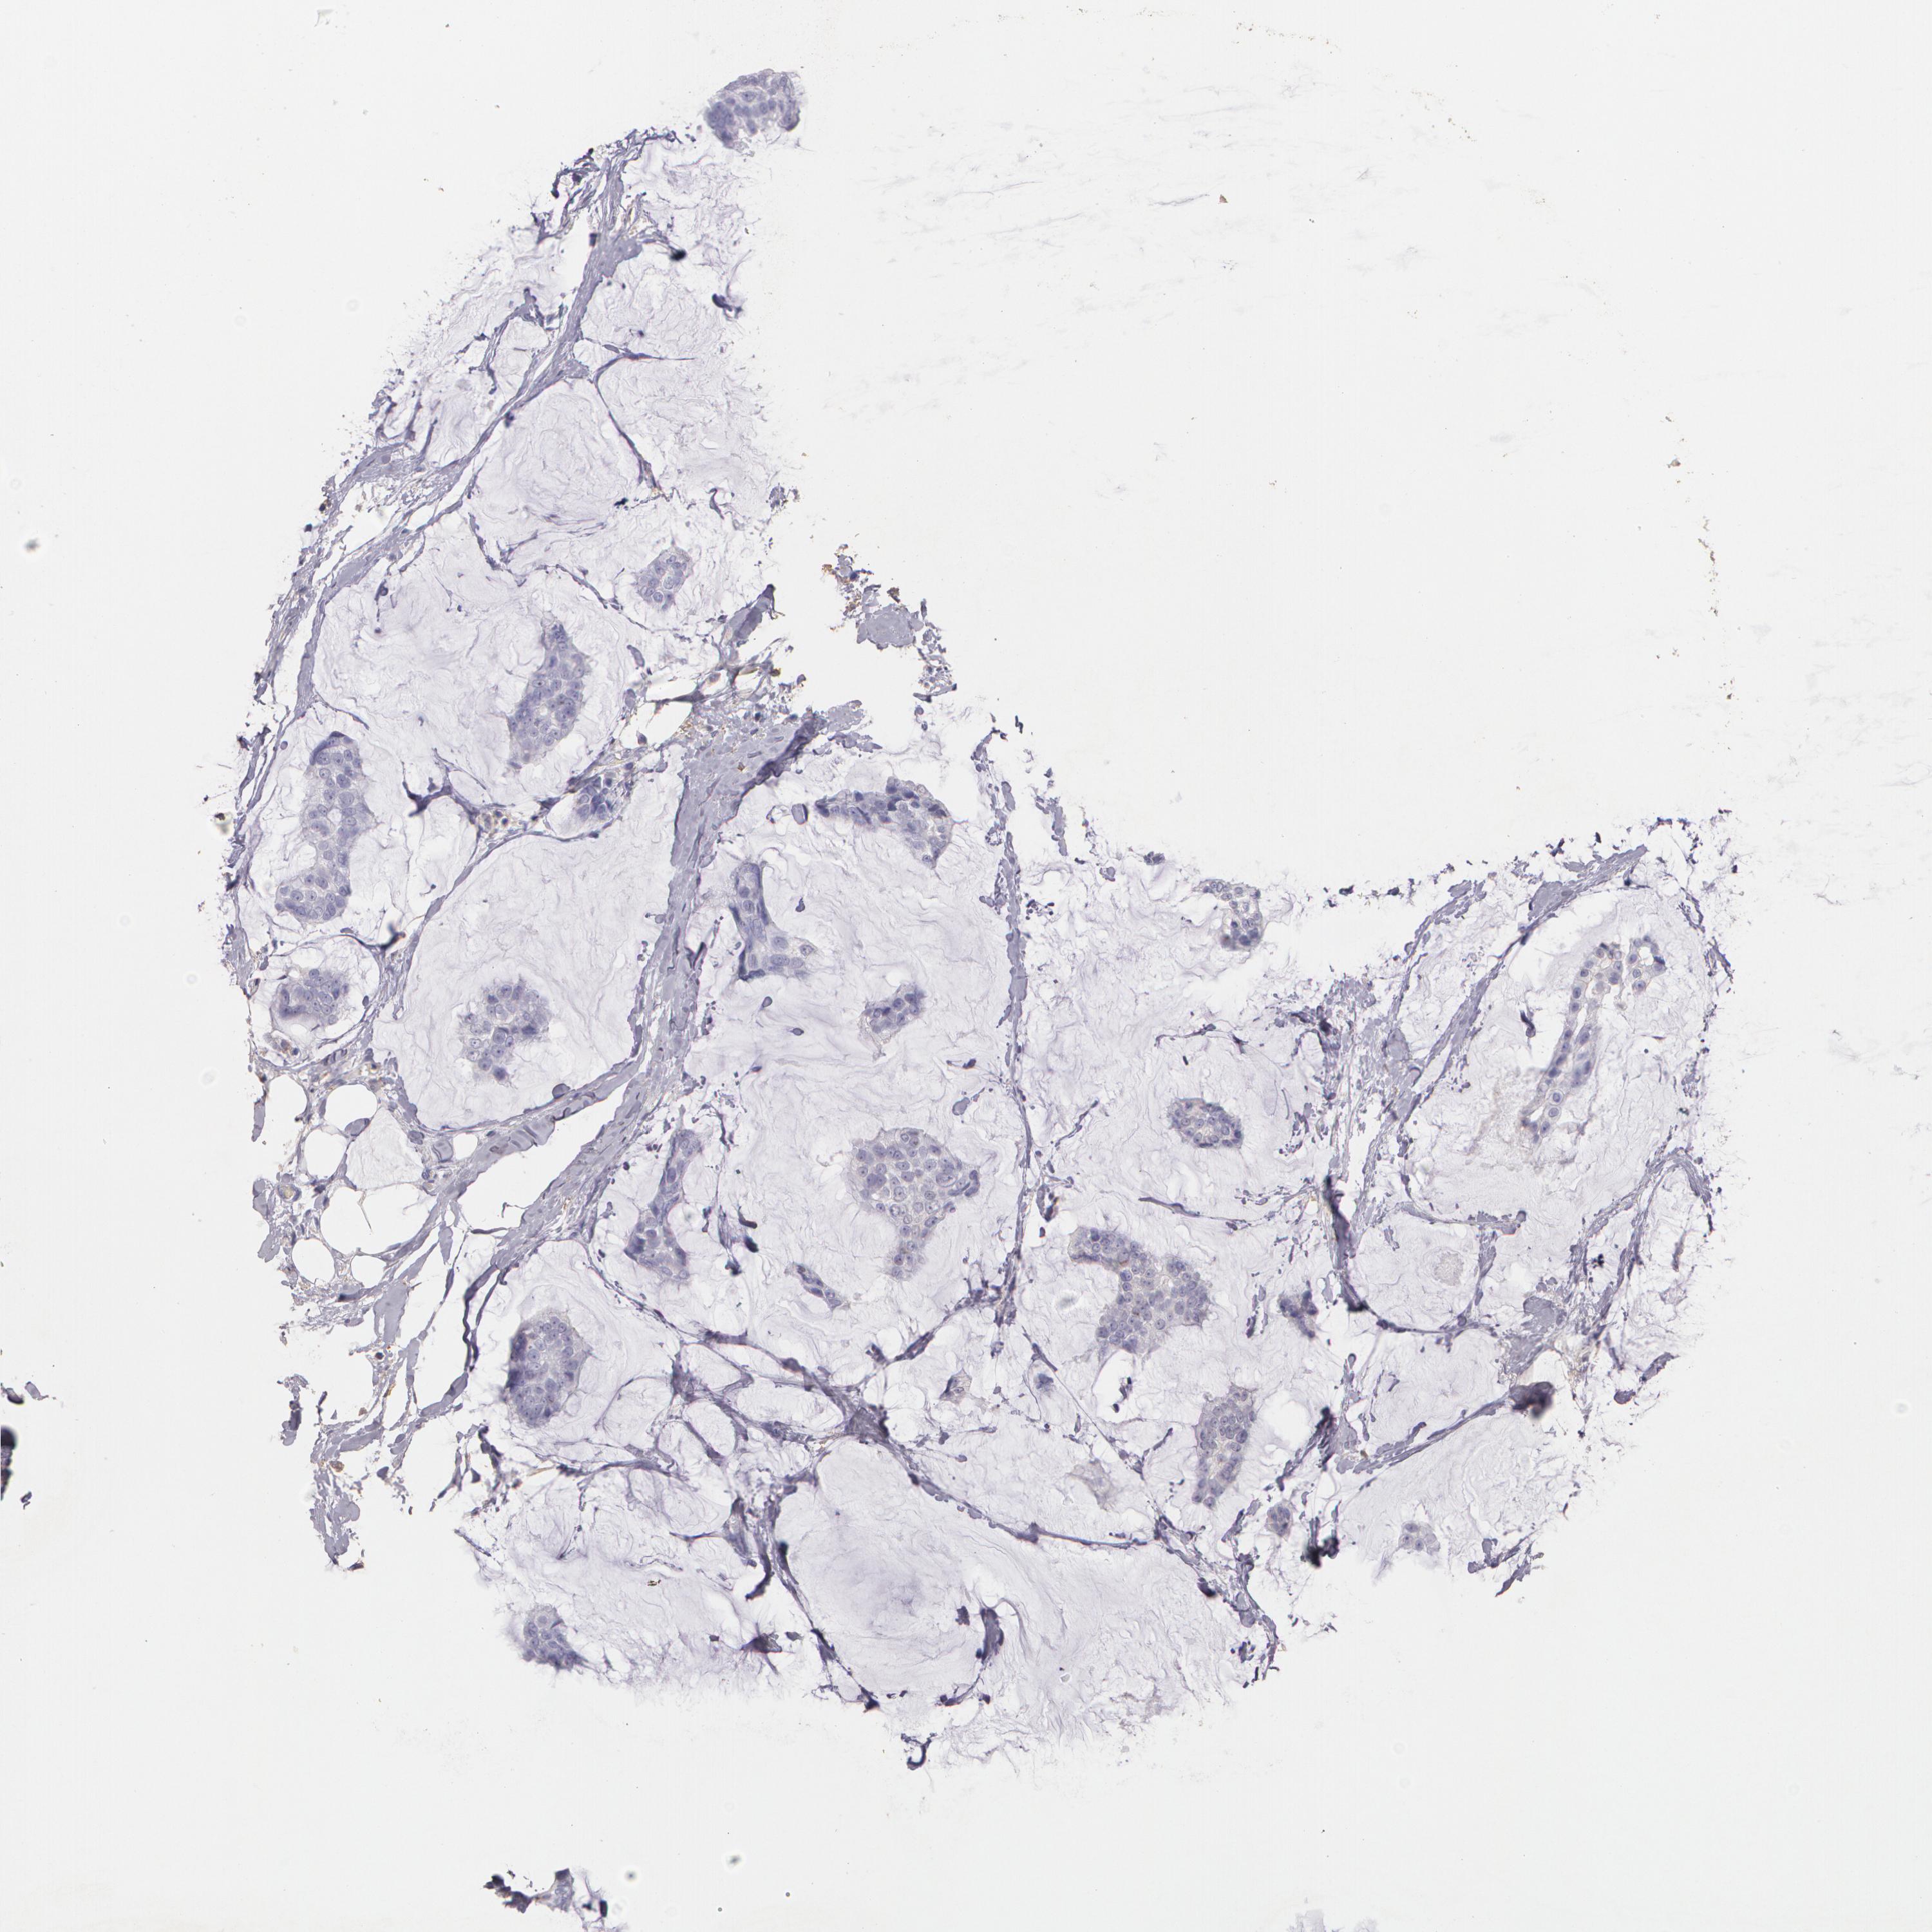

BRCA TCGA BRCA VALIDATION PROTEIN EXPRESSION

Breast cancer

Human cancer